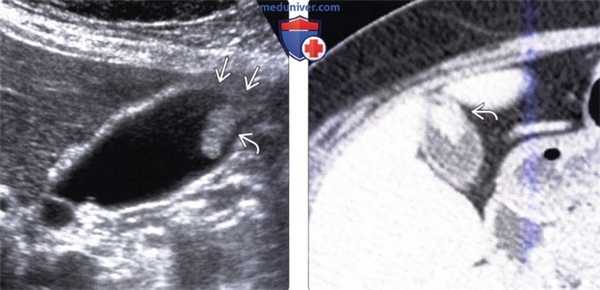

(Левый) Положение пациента на левом боку. На продольном УЗ срезе визуализируется холестериновый полип; стенка желчного пузыря не изменена.

(Правый) Тот же пациент. Некоторое время спустя выполнена КТ с контрастным усилением. На сагиттальной томограмме определяется холестериновый полип, отмечается легкое неспецифическое утолщение стенки желчного пузыря.